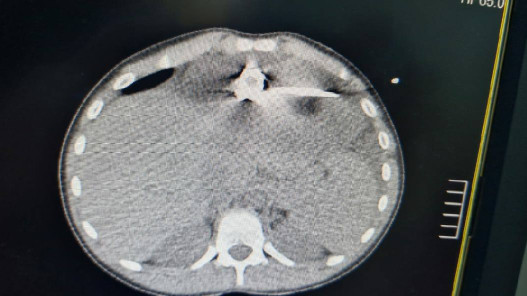

وقال مدير مستشفى الأميرة بسمة إبراهيم شهابات السبت، إن هذه الحالة الطبية تسمى “انصباب التامور”، وهو تجمّع سوائل حول القلب داخل غشاء التامور، ما أدى إلى تطور الحالة نحو “انضغاط القلب”، وهي حالة طارئة تستدعي التدخل العاجل فورا خلال ساعات قليلة للحفاظ على حياة المريض.

وأضاف أنه جرى وضع أنبوب تصريف باستخدام تقنيات متقدمة وتوجيه إشعاعي دقيق للحالة، ما مكّن من إزالة السوائل من القلب، واستعادة العلامات الحيوية للمريض خلال دقائق معدودة، حيث زال الخطر عنه وأصبحت حالته الصحية جيدة جدا.